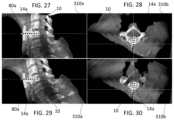

FIG.27 depicts a sagittal view of a CT scan with computer graphics overlaid to help the user select the appropriate detent for the uniplanar drill guide from a surgical planning screen according to one embodiment;

FIG.28 depicts an axial view of the CT scan ofFIG.27;

FIG.29 depicts a sagittal view with the graphic having a different trajectory and detent for the uniplanar guide thanFIG.27; and

FIG.30 depicts an axial view ofFIG.29.

In yet another embodiment, the software tools may be used in conjunction with theuniplanar drill guide50, for example.FIGS.27-30 show an embodiment of a software feature that may allow the user to select the appropriate tooth or detent for the uniplanar drill guide50 from thesurgical planning screen310 of therobot302. The user adjusts the placement of the foot of thedrill guide50 relative to the spine or that placement is auto-set based on image processing and as the user adjusts the slice plane, the corresponding drill guide position is displayed.

The software tools may assist in pre-planning or during surgery to aid in selection of the desired notch of thetooth array80 on theuniplanar guide50. As best seen inFIGS.27-30, an adjustable interface allows the user to select the angle of the plannedchannel14athrough thevertebra10, and then provides feedback on the appropriate notch on theuniplanar drill guide150. Feedback could be visual, showing arepresentation80aof thetooth array80 and specific notch where the tool should be set, or could be numerical, specifying the notch number that thedrill guide150 should be set to. Such a software interface also allows the implant length to be selected and the distance from entry to spinal canal to be accurately measured, allowing thelockable depth stop200 to be accurately set, for example.